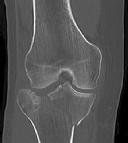

**CLINICAL SITUATION**

Figures 1 and 2 are the radiographs of a 35-year-old man who is brought into the emergency department after a motor vehicle collision. He is complaining of isolated knee pain. Examination reveals swelling, blood filled blisters, popliteal ecchymosis, joint line pain, and limited knee joint motion. His pulses and sensation are normal.

Figures 3 through 8 are the axial and sagittal CT scan sections of the injury. Intra-operative patient positioning for definitive fixation should be

The surgical approach for definitive reduction and stabilization of this pattern is

Figures 1 through 3 are the radiographs of a 25-year-old man who is brought to the emergency department after a motorcycle collision. He is complaining of isolated knee pain. Examination reveals swelling, popliteal ecchymosis, joint line pain, and limited knee joint motion. His pulses and sensation are normal.

Figures 4 through 8 are the axial and coronal CT scan sections of the injury. Intra-operative patient positioning for definitive fixation should be